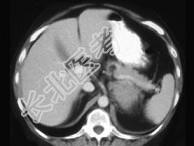

- 单项选择题女,47岁, 满月脸、向心性肥胖伴高血压1个月,请结合所提供图像, 作出诊断 ( )

A、左肾上腺腺瘤

B、左肾上腺腺癌

C、左肾上腺转移瘤

D、左肾上腺嗜铬细胞瘤

E、左肾上腺增生